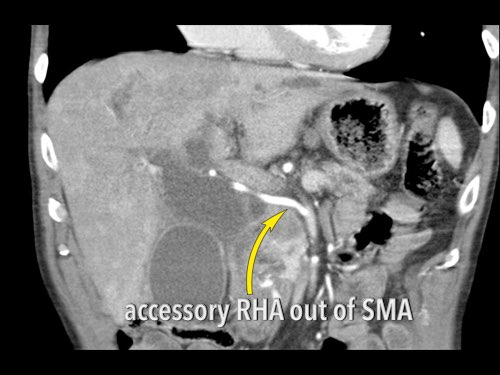

Ở những bệnh nhân dự kiến phẫu thuật tụy, điều quan trọng là cần đặc biệt chú ý tìm kiếm nguyên ủy bất thường của động mạch gan phải hoặc động mạch gan chung.

Các động mạch này xuất phát từ phía phải của động mạch mạc treo tràng trên (SMA) và đi qua vùng lân cận đầu tụy, làm tăng nguy cơ xâm lấn của khối u hoặc tổn thương do phẫu thuật.

Tần suất được ghi nhận của các bất thường đặc hiệu này lần lượt là 11-21% và 0,5-5%.

Các hình ảnh mặt phẳng đứng ngang của một bệnh nhân có khối u ở đầu tụy và động mạch gan phải phụ thêm.

Lưu ý sự áp sát của động mạch phụ thêm bởi khối u.